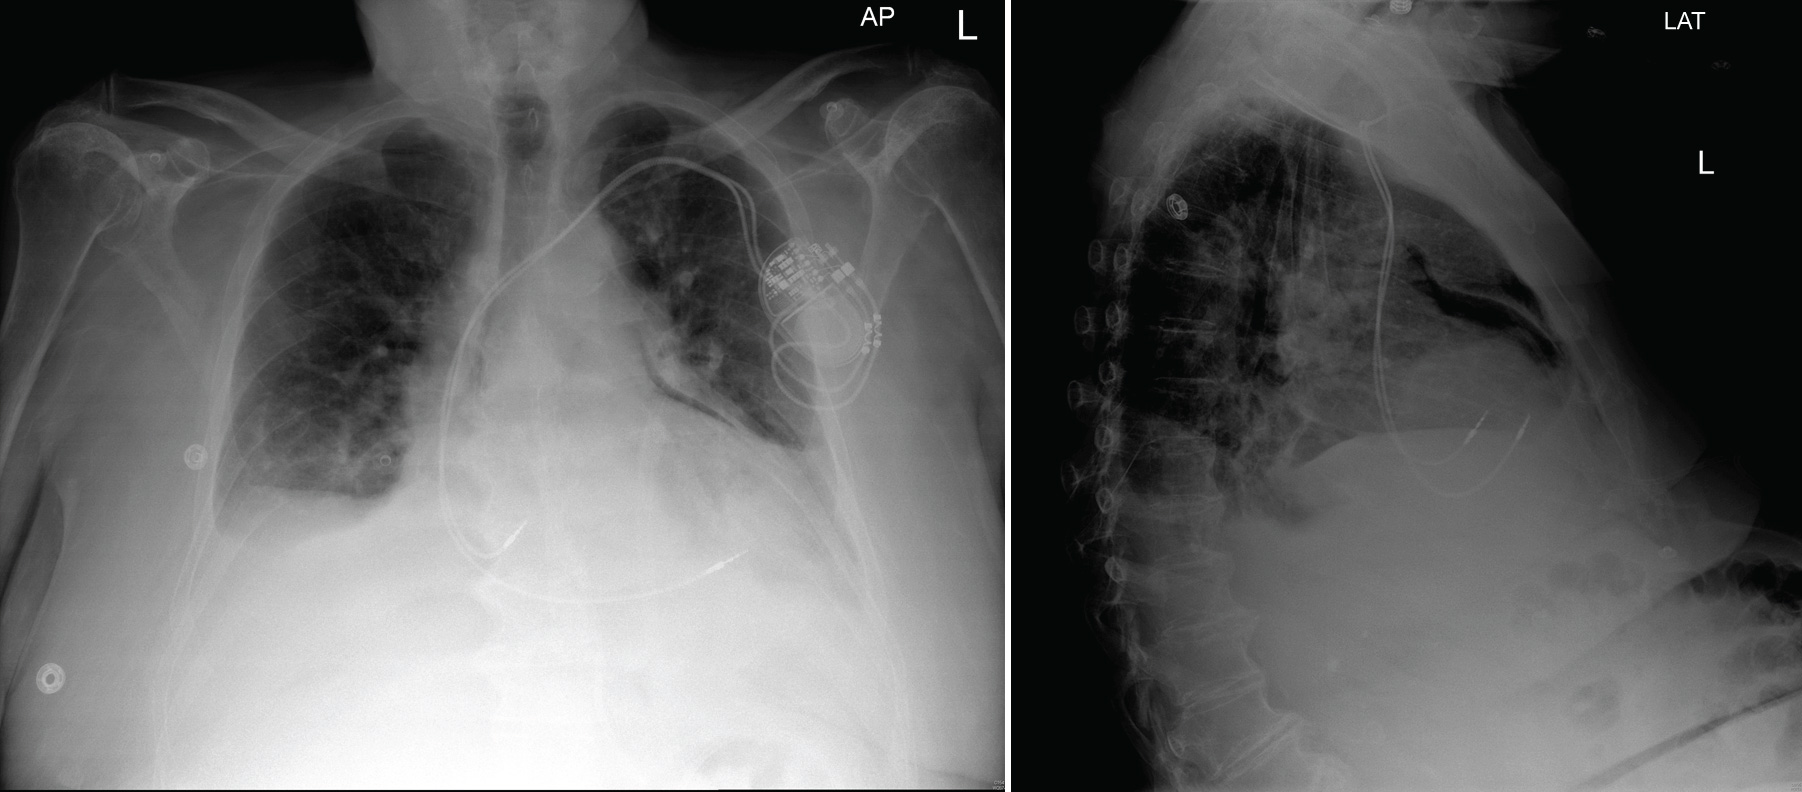

A Chest X-Ray You Don't See Everyday

... unless, of course, you're a cardiac electrophysiologist:

An anterior-posterior (AP) and lateral (LAT) chest radiograph

(Click image to enlarge)

-Wes